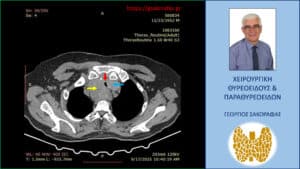

Αξονική τομογραφία – εγκάρσια διατομή. Ο λίαν διογκωμένος και καταδυόμενος δεξιός λοβός (κίτρινο βέλος) απωθεί προς τα αριστερά την τραχεία (κόκκινο βέλος), που συμπιέζεται και από τον λιγότερο διογκωμένο αριστερό λοβό (μπλε βέλος), με αποτέλεσμα την στένωση του αυλού της